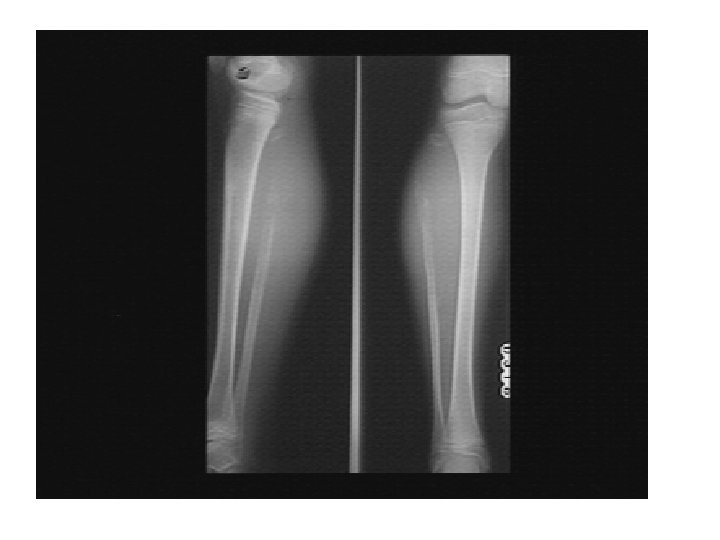

Rickets • Rickets is the softening and weakening of bones in children, usually because of an extreme and prolonged vitamin D deficiency. • Some skeletal deformities caused by rickets may need corrective surgery.